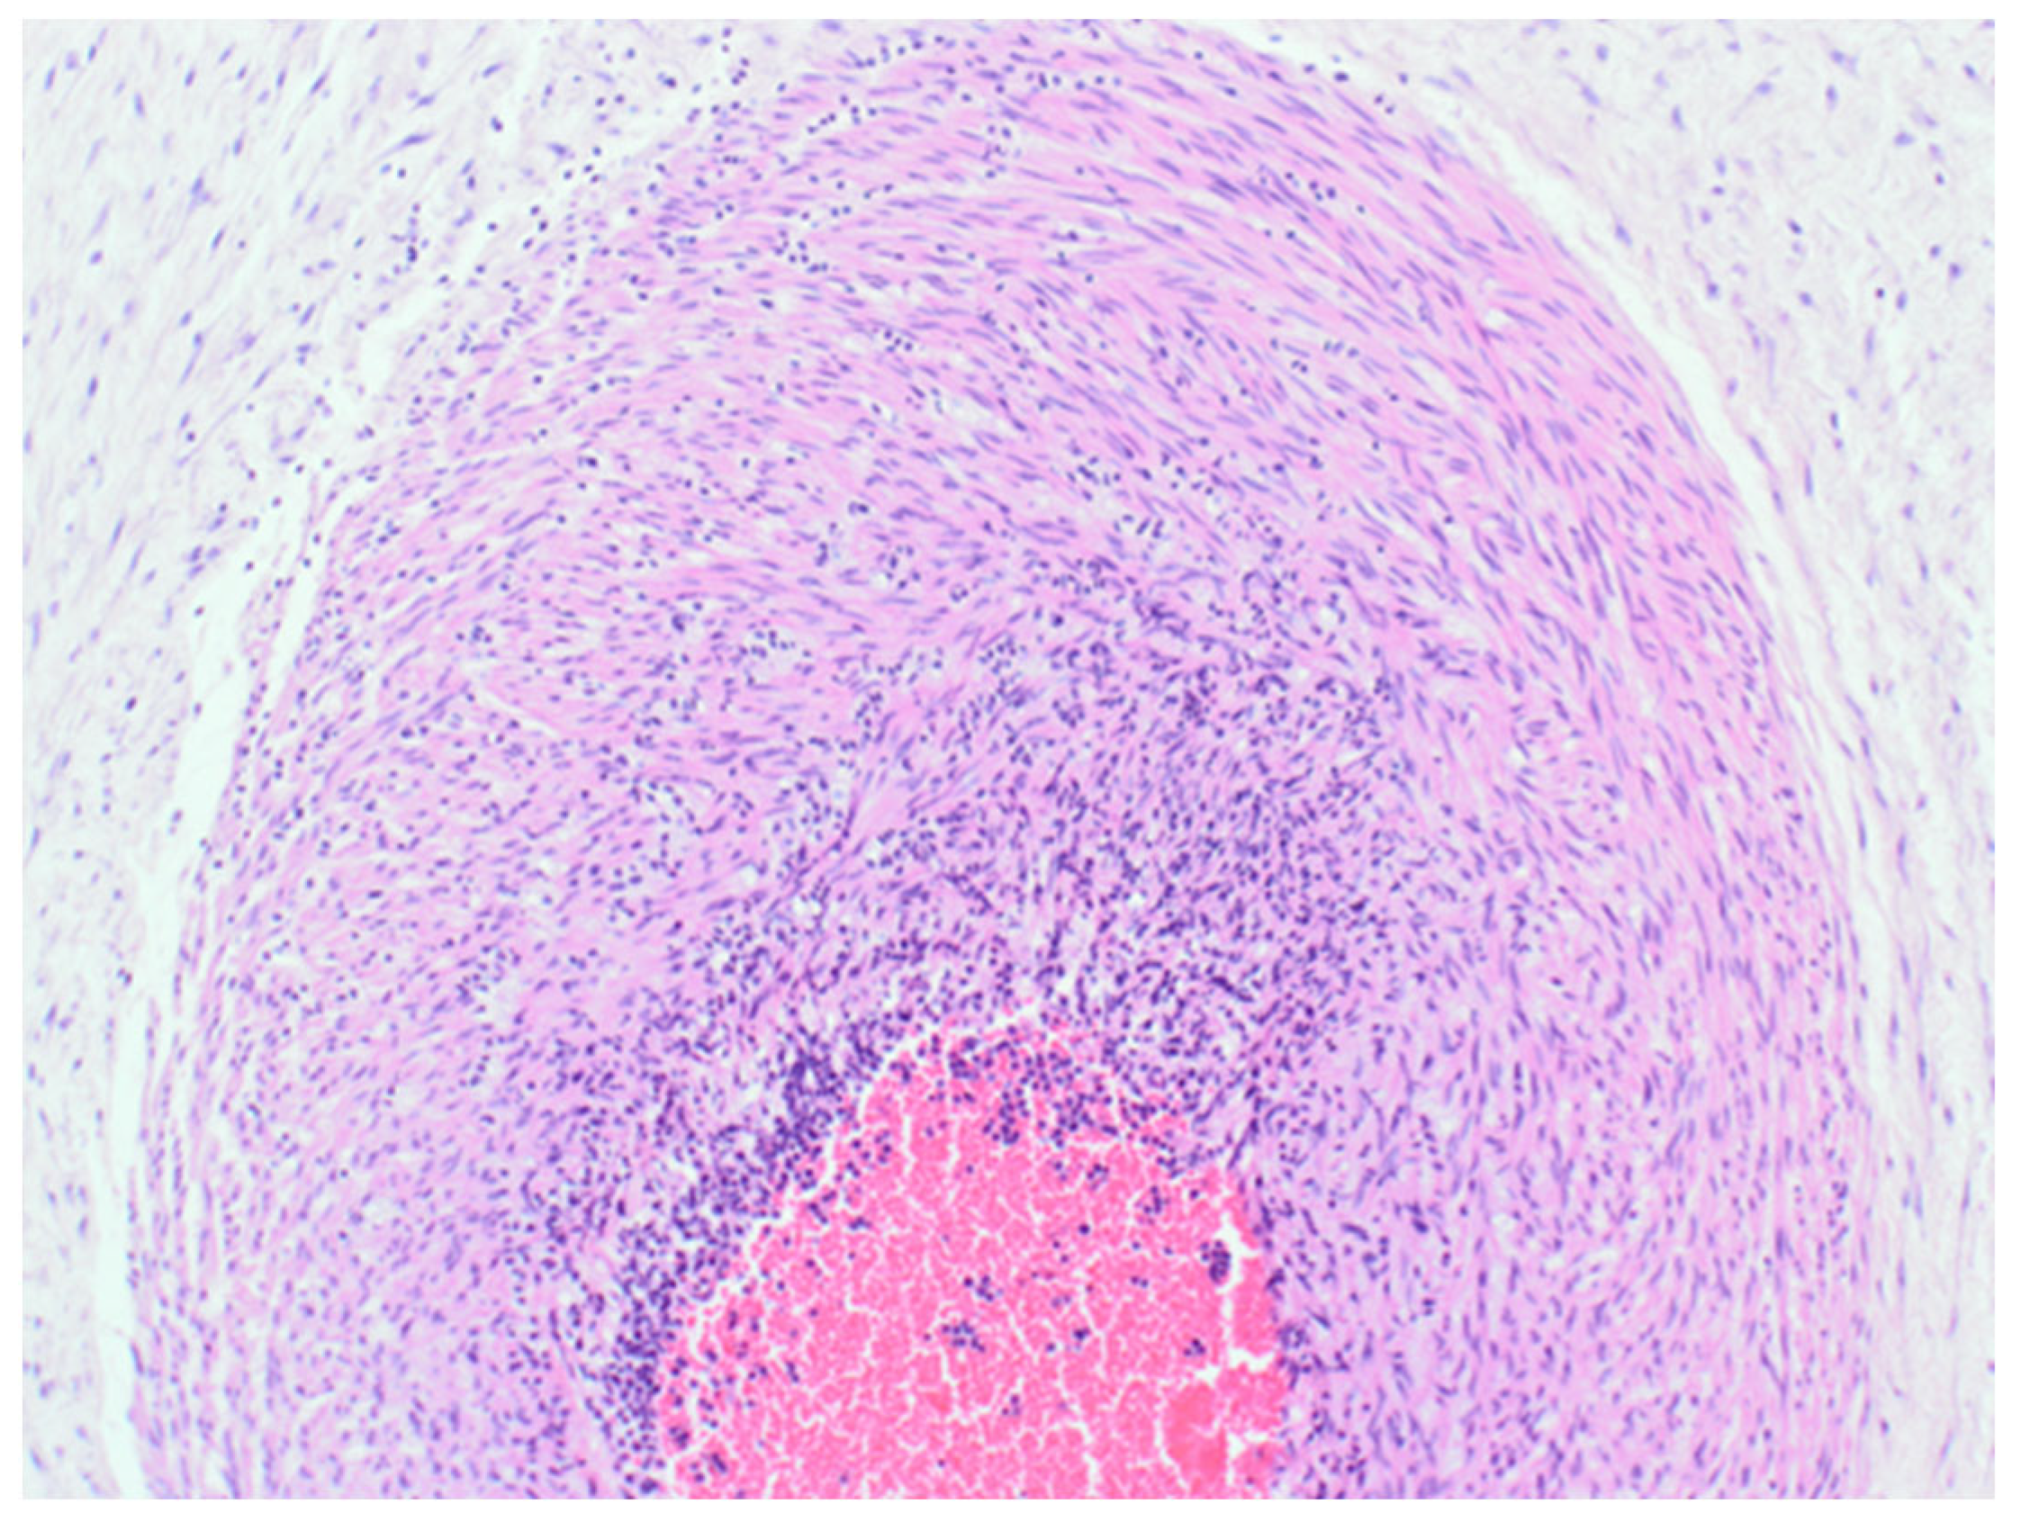

The sample received in the histopathology department was a disc of placenta and membranes with an eccentrically inserted umbilical cord. The placenta trimmed of the membranes weighed 145 mg. The membrane appeared complete and was mostly translucent but with patchy areas of opacity. Microscopy revealed patchy severe acute chorioamnionitis and prominent clusters of Gram-positive filamentous bacteria, which were noted on the surface of the membranes in routine haematoxylin and eosin (H&E) (Figure 1) as well as with Periodic Acid Schiff (PAS) staining (Figure 2). Aggregates of the Splendore–Hoeppli reaction, which are sulphur granules formed from masses of gram-positive bacteria with branching filaments, are also identifiable in Figure 2. The infective organism was revealed to be gram-positive (Figure 3). In this specific case, the microscopic examination indicated the presence of acute inflammation due to an uncommon organism—Actinomyces spp. infection. Sections of the umbilical cord revealed acute inflammation (funisitis), but no organisms were seen in the umbilical cord (Figure 4). During the follow-up visit, the mother did not demonstrate any symptom or sign of infection, her recovery was uneventful, and she remained well during the subsequent reviews.

Figure 3.

Gram stain (400×) showing dense aggregates of Gram-positive organisms representing Actinomyces spp. (red arrows) in the placental membranes.